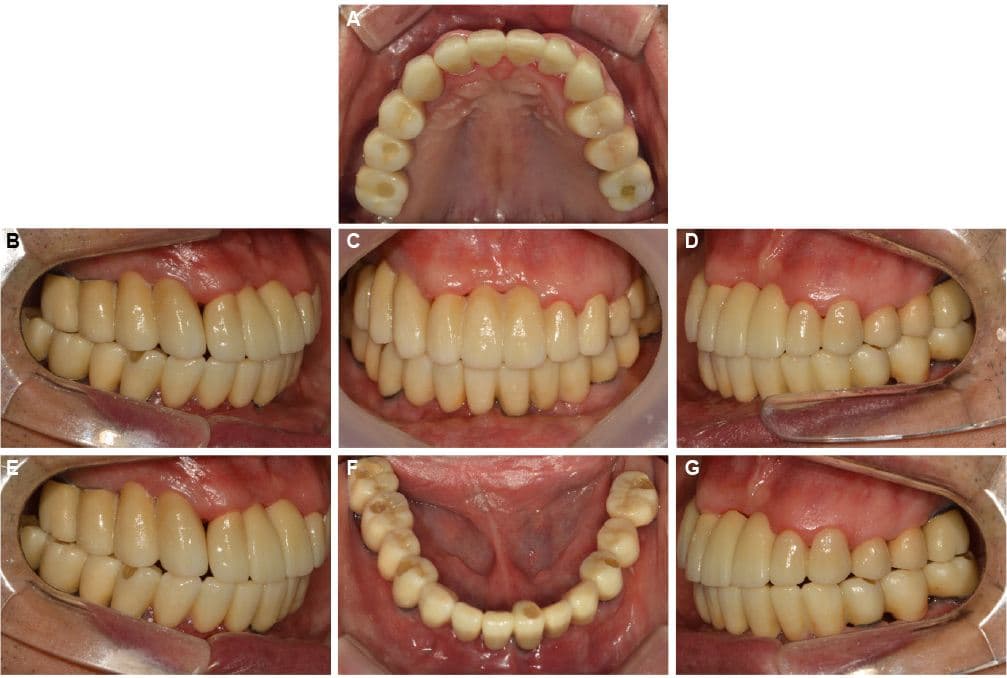

Phục hồi toàn hàm

Những trường hợp sức khỏe răng miệng bị hủy hoại hoàn toàn

được phục hồi trở lại cuộc sống bình thường

Điều trị tổng thể bởi bác sĩ chuyên khoa Phục hình

Bác sĩ phục hình của chúng tôi kết hợp tối ưu các phương pháp điều trị bao gồm Implant, răng sứ và cầu răng để tạo ra kết quả tốt nhất với chi phí hợp lý.

Sau

Phục hồi toàn hàm · Ông S●● · Nam, 70 tuổi

Phục hồi toàn hàm · Ông O●● · Nam, 60 tuổi